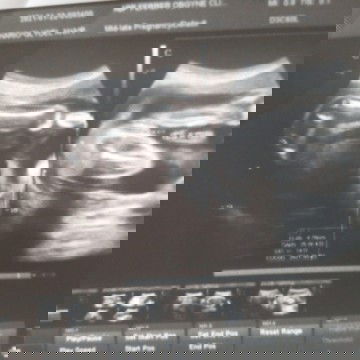

Ultrasound

24 weeks And finally, It's baby girl 🤰thank god for the gift of life. 🙏💝🥰 #1stimemom #firstbaby